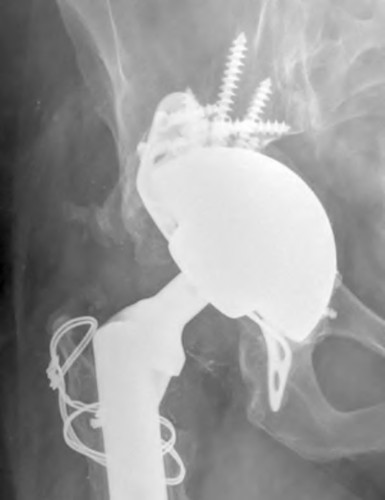

An 80-year-old female presents following a fall from standing. She was an active, independent, community ambulator prior to this event. Past surgical history is significant for a left total hip arthroplasty 10 years prior. A left hip XR is obtained and shown in Figure A. A CT is obtained and demonstrates a displaced transverse acetabulum fracture with medial cup migration. There is no evidence of femoral component loosening or fracture. There is no concern for infection and all inflammatory markers are within appropriate limits. Which treatment is most appropriate?